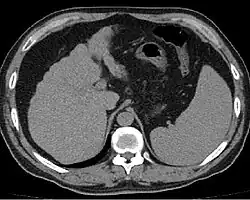

Other scans include CT of the abdomen and MRI.[45] A CT scan is non-invasive and may be helpful in the diagnosis.[45] Compared to the ultrasound, CT scans tend to be more expensive. MRI provides excellent evaluation; however, it is expensive.[45]

Liver cirrhosis on CT imaging of the abdomen in transverse view